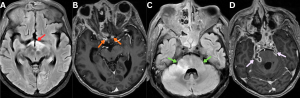

Fig 10: Cases 1–3: Intracranial Abscesses....

Case 1 -

A 48-year-old male with uncontrolled diabetes mellitus and recent corticosteroid use presented with fever, headache, and altered sensorium.

Axial diffusion-weighted imaging (DWI) and apparent diffusion coefficient (ADC) images (A), along with a post-contrast T1-weighted MRI image (B), demonstrate a diffusion-restricting abscess in the right temporal lobe (red arrow) with peripheral rim enhancement (blue arrow) and a central nonenhancing core, showing direct continuity with adjacent sinusitis (green arrow).

..........Case 2 -

A middle-aged male with uncontrolled diabetes mellitus and recent corticosteroid use presented with fever, headache, and altered sensorium.

Axial T2/FLAIR MRI image (C) demonstrates near-complete opacification of the ethmoid sinuses (orange arrow). Axial post-contrast T1-weighted MRI image (D) demonstrates a peripherally enhancing subdural collection along the anterior falx with additional enhancing collections in the basifrontal region (white arrow).

...........Case 3 -

A 48-year-old diabetic male presented with fever, headache, and new-onset behavioral changes.

Axial DWI image (E) and sagittal post-contrast T1-weighted MRI image (F) demonstrate a diffusionrestricting abscess in the left frontal lobe (yellow arrow) with peripheral rim enhancement and a central nonenhancing core (pink arrow), showing direct extension from ethmoidal sinusitis (blue arrow).